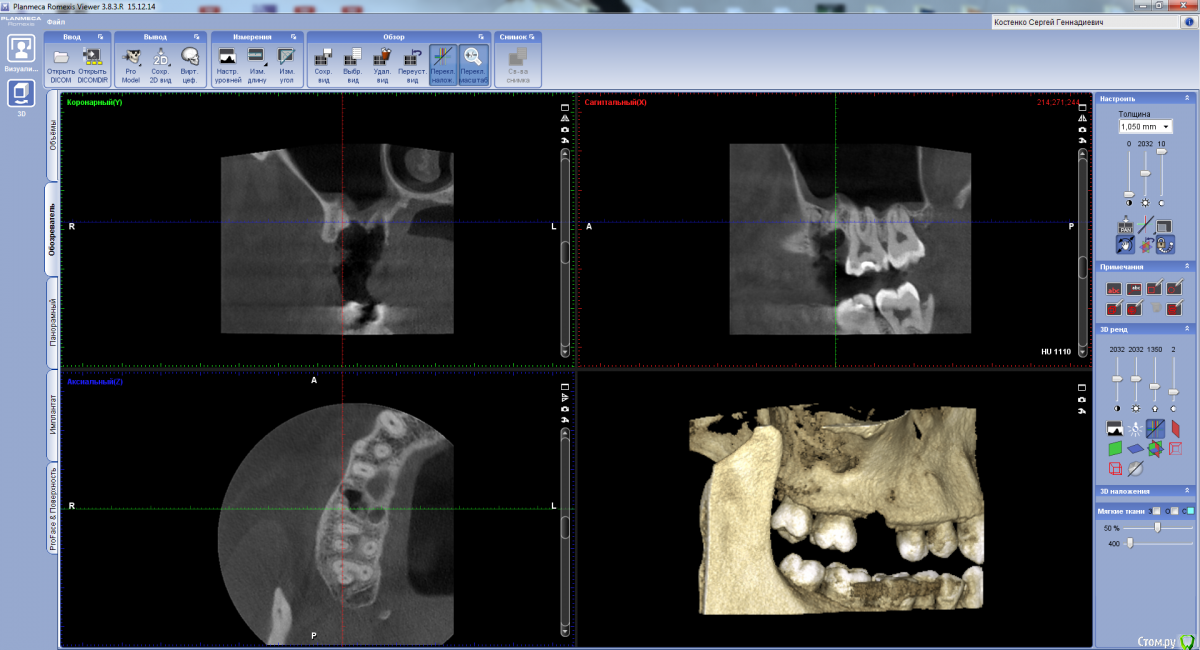

Сергей Кривой Рог Опубликовано 4 мая, 2018 Поделиться Опубликовано 4 мая, 2018 Сегодня пошол в больницу с проблемой треснул зуб. Сказали нужно удалять отправили к хирургу. Тот обезболил и начал рвать.....сказал тяжелый случай тянул, крутил, потом начал стучать молотком , аж затошнило, после начал что то бурить, и отправил на снимок. Сказал 2 или 3 корня удалил один не может. Отправил в другую больницу... Там отправили на КТ и сказали нужно делать операцию ценой 200 долларов. Цена для меня велика. Мне кажется меня розводят на деньги. Посоветуйте что делать. Сказали что может теперь борщ через нос выливаться. Ссылка на комментарий

kramer Опубликовано 4 мая, 2018 Поделиться Опубликовано 4 мая, 2018 (изменено) А что делать что надув щеки воздух в нос идет?? может затянутся? Не надувать пока щеки. Обратитесь к врачу. После того как остатки корней будут удалены, хирург оценит размер перфорации (между гайморовой пазухой и полостью рта) и определит тактику лечения. Может, просто затампонирует ее на время, может, будет пластику делать. Изменено 4 мая, 2018 пользователем kramer Ссылка на комментарий